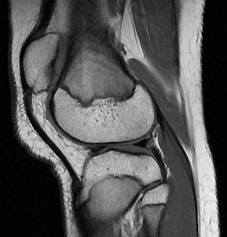

Normal Knee

Normal Cruciate Ligaments. CKC MRI

Normal cruciate ligaments

Normal articulating surfaces